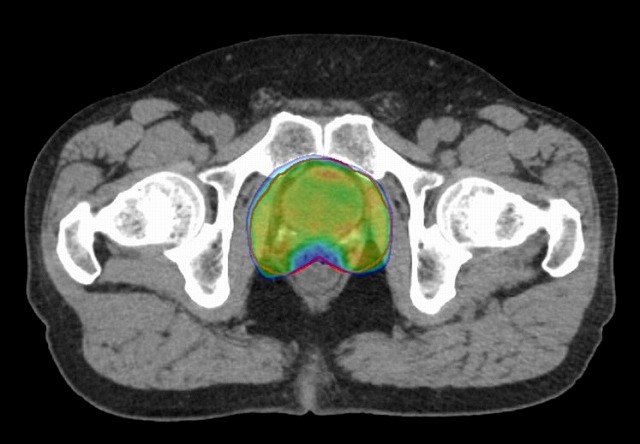

IMRTを用いて直腸の線量を減らして前立腺に照射。